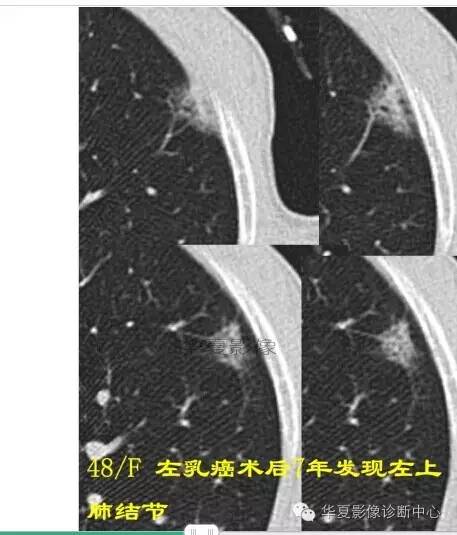

磨玻璃结节良恶性影像分析策略磨玻璃结节良恶性影像分析策略 这个按常规看到血管由凹陷处进去常规95%考虑癌,可是这里却不是

除非说这里GGO边缘稍模糊一些

宽基底与胸膜相连

近端有模糊的高密度影

典型病例,没给病史